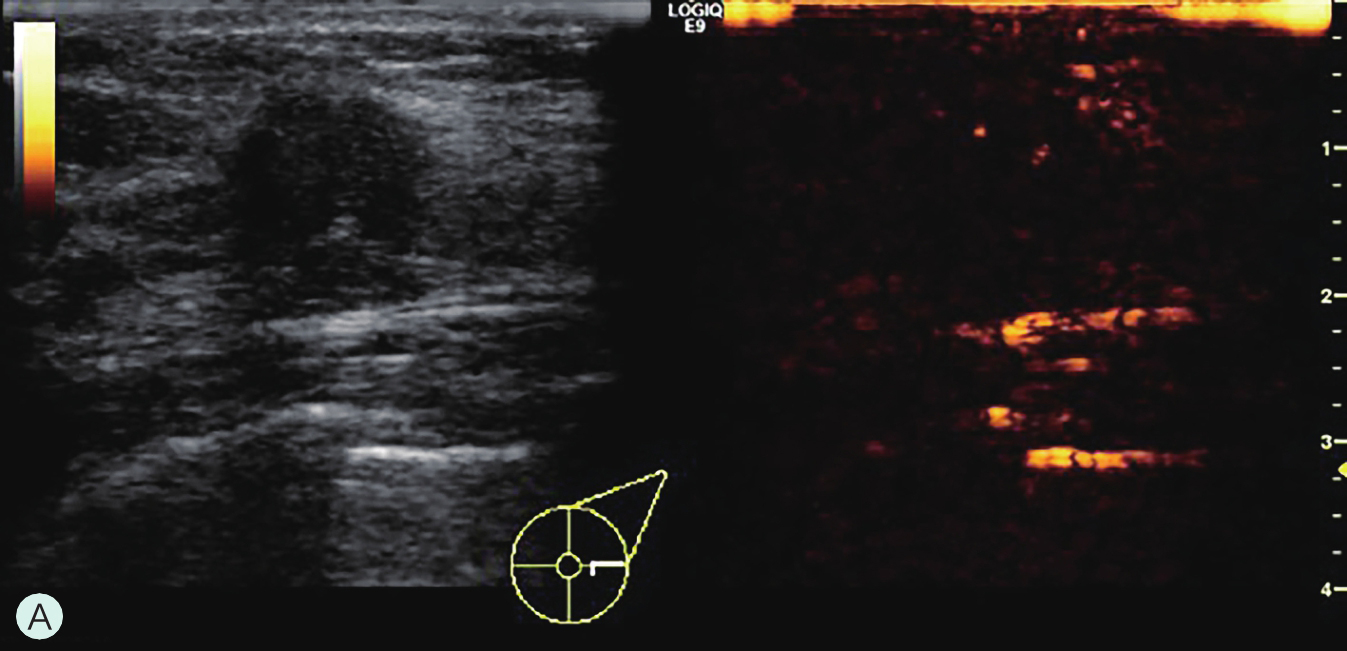

图2-2-8 分析与判读

A.同步测量病灶大小与高增强范围;B.勾勒病灶与增强范围;C.定量分析